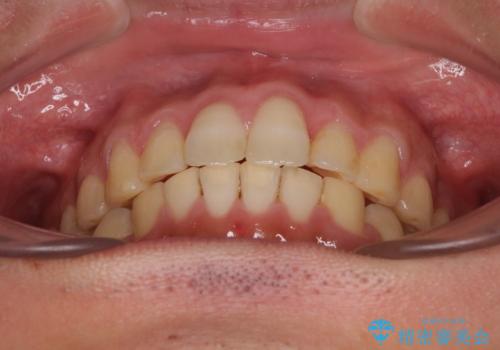

捻れて飛び出した前歯 インビザラインで整った前歯に

歯と歯の間を削ることでうまくスペースコントロールでき、また、毎日22時間以上しっかりとマウスピースを装着していただいたので、スムーズに治療が進みました。

治療途中で転勤となり、遠方からの通院となったため、来院間隔空いてしまいましたが、2年間で終えることができました。